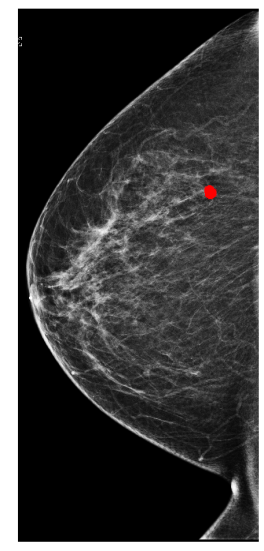

In Figure 1, we show an annotation and the corresponding prediction using an X-101 model. The model accurately predicts a malignant lesion with high probability (0.99). It also predicts a benign lesion with low probability (0.36) for which there is no ground-truth annotation. These bounding boxes can highlight suspicious regions and help radiologists understand predictions from our models.